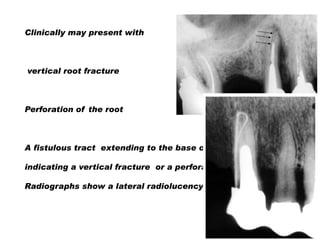

Clinically may present with

vertical root fracture

Perforation of the root

A fistulous tract extending to the base of the post

indicating a vertical fracture or a perforation site

Radiographs show a lateral radiolucency

Clinically may presentwith vertical root fracture Perforation of the root A fistulous tract extending to the base of the post indicating a vertical fracture or a perforation site Radiographs show a lateral radiolucency